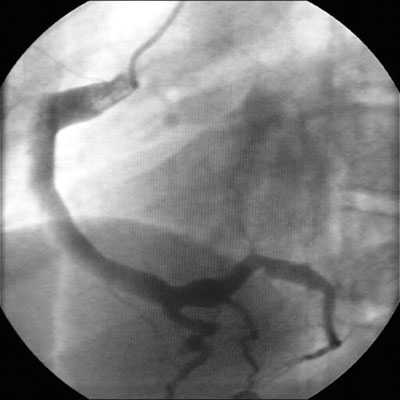

Kawasaki disease

Coronary artery ectasia

BMJ Case Reports 2009; doi:10.1136/bcr.10.2008.1113